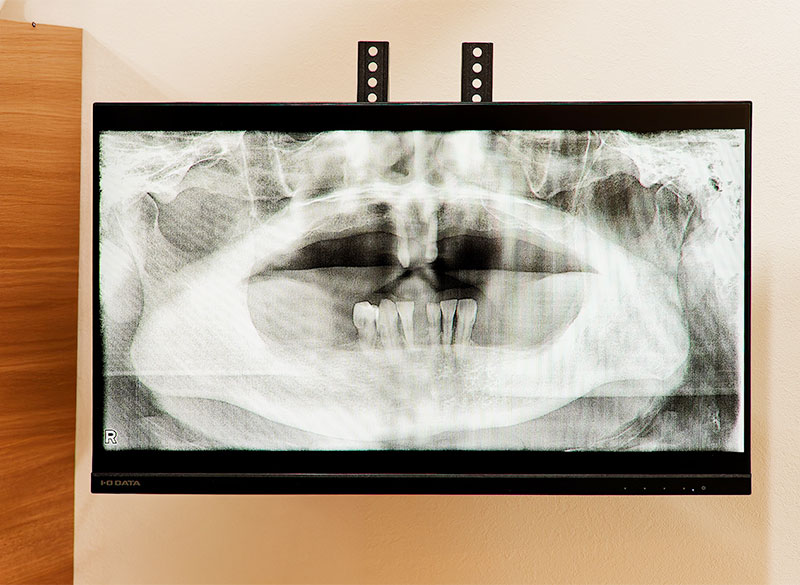

デジタルレントゲン・歯科用CT

デジタルレントゲン・歯科用CTは、お口の中や顎の骨を立体的に確認できます。骨の厚みや神経、上顎洞の位置まで把握できるため、抜歯やインプラント治療の前にリスクを見極め、無理のない計画を立てられます。画像はモニターで確認できるので、わかりやすいご説明に役立ちます。